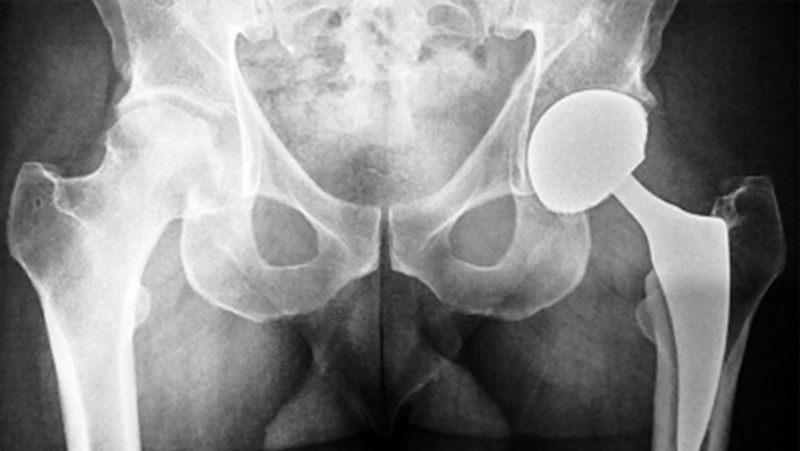

图3 术后三年,右侧股骨头轻度塌陷